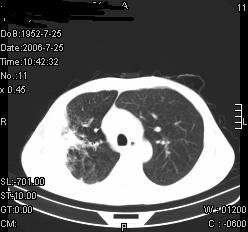

患者,男,54岁,咳嗦,咳痰20天。抗炎治疗2周。现esr76mm/h,目前患者症状明显好转,但发现两次ct片未见明显变化。两次分别做与7.25、7.31。第一次诊断右肺上叶炎症累计胸膜。大家看,从影像上内排除结核吗?

结核的可能性非常大,右上肺病变应该考虑干酪性肺炎。理由:

1.纵隔内多发淋巴结肿大。

2.esr76mm/h。

3.虽经抗炎治疗肺窗病灶有所吸收、减小,但纵隔窗病灶形态、密度、范围无明显变化。如果是单纯的大叶性肺炎,“抗炎治疗2周,目前患者症状明显好转”病灶应该基本消散了,至少也处于吸收消散期,密度变淡、范围变小。同时本病例所示其内的密度不均匀,见多发大小不一空洞样影也不符合大叶性肺炎吸收消散期表现。

病灶特点:片状 索条 结节混杂影,部分融合,密度不均,广泛累及相应胸膜.

临床治疗;二周未吸收.但症状好转.

多考虑:肺结核.